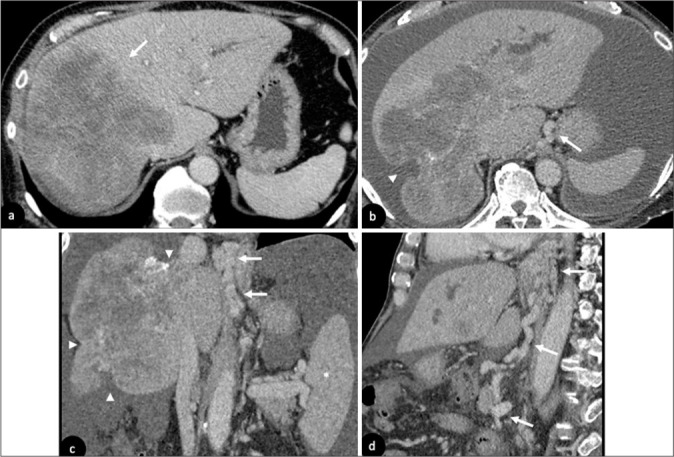

在过去的几十年里,化疗的使用彻底改变了癌症的治疗。肝毒性在不同类型的化疗药物中普遍存在。这篇图片综述的目的是阐明各种化疗相关肝实质改变在不同成像方式下的放射学特征,并通过代表性病例展示这些肝损伤模式的潜在并发症。早期识别这些肝脏疾病可以及时采取临床行动,从而优化管理并避免严重并发症。

The use of chemotherapy has revolutionized the management of cancer in the past decades. Liver toxicity is commonly observed among different types of chemotherapy drugs. The aim of this pictorial review is to illustrate radiological features of various chemotherapy-associated hepatic parenchymal changes in different imaging modalities and to demonstrate potential complications of these liver injury patterns with representative cases. Early recognition of these liver conditions allows prompt clinical action to be taken, thus optimizing management and avoiding severe complications.